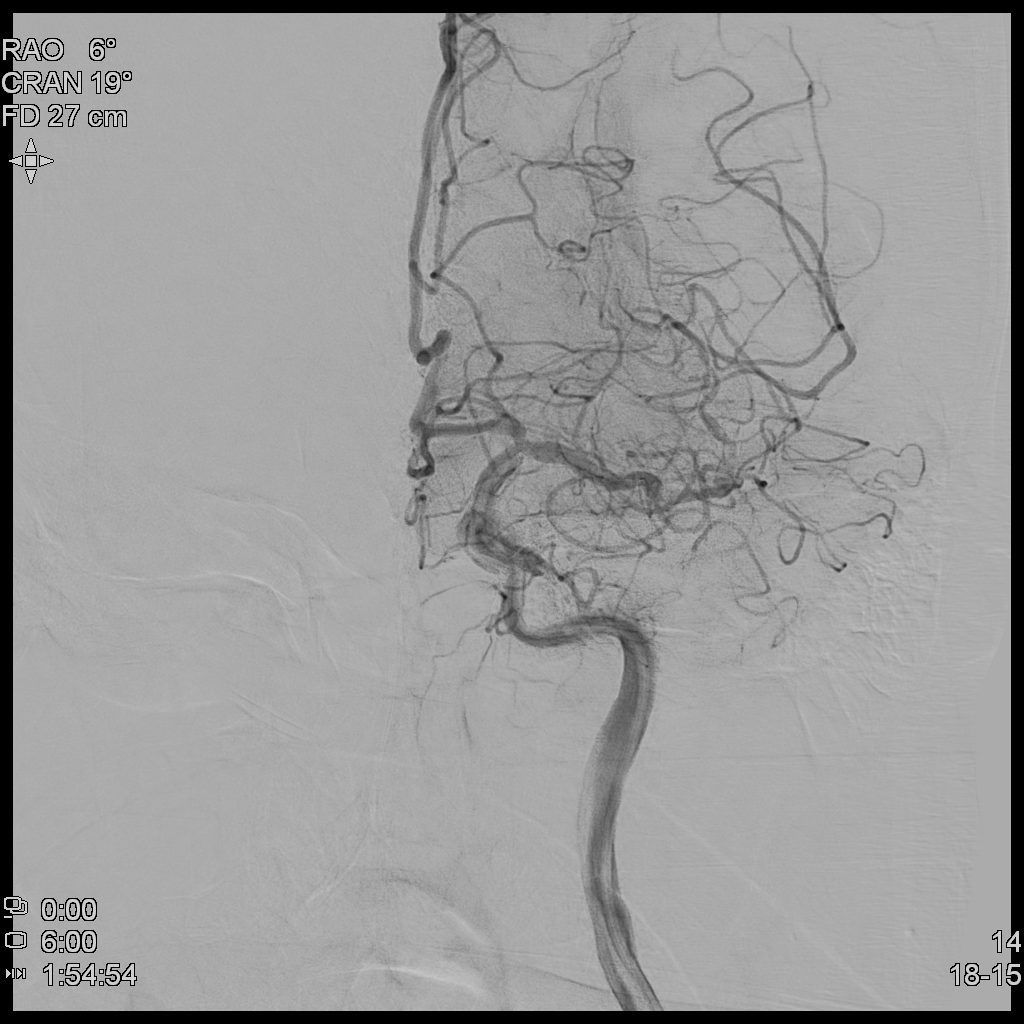

때문에 TFCA(Trans-Femoral Cerebral Angiography)를 통해 환자 뇌혈관의 막힌 혈관을 뚫어보고자 하였고, 환자는 1시간여만에 뇌혈관조영술을 시행하게 되었다.

뇌혈관조영술(TFCA)을 통해 어느정도 막힌 혈관의 일부를 뚫어내고 이후 혈류가 전달되는 모습을 확인하였다.